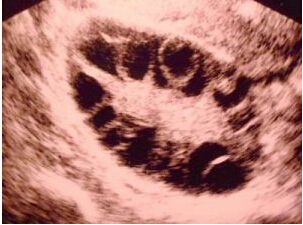

患有多囊卵巢(PCOS)的女性,卵巢内看上去的卵泡挺多,但就是不排卵。这就好比看到藤上挂了一串“葡萄”挺诱人,但这串“葡萄”却一直不成熟。如果给它施点肥帮它快点长大(促排卵),很有可能这一串“葡萄”一下成熟好几十个,从而引发卵巢过度刺激综合征(OHSS)。而OHSS在自然情况下是不会发生的,只有在促排卵的时候才有可能发生,这是由于促排期间使用了刺激卵巢的药物,很可能由于药物的刺激导致卵巢的体积变大,使得卵泡过度生长。

促排卵治疗,B超检查卵巢体积增大,双侧卵巢有多个小卵泡但却不能发育为成熟的卵泡,需要用药物来促卵泡发育诱发排卵。常用药有来曲唑,为多囊卵巢综合征不育患者的常用药物。还可以加用HMG、FSH治疗,但是使用过程中应该避免卵巢过度刺激的发生,必须在专业的生殖医生的监护下使用。